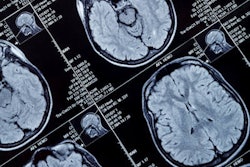

MRI scans revealed structural brain changes in a group of middle-aged adults who were exposed to lead as children. The findings were part of a long-term study published on November 17 in JAMA.

MRI scans revealed the study population had approximately 1 cm2 less cortical surface area and 0.1 cm3 less hippocampus volume -- regions that affect memory, learning, and emotion. Participants also lost an average of two IQ points for each 5 µg/dL more lead they carried as children.